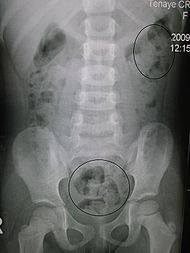

در این بررسی معمولاً بیمار تعداد 60 عدد از قرصهای كوچكی را میخورد و پس

از چند روز با عكسبرداری ساده شكم طول مدت عبور مواد از روده بزرگ تعیین

میگردد. براساس نتیجه این كار در مورد درمان طبی و یا جراحی روده بزرگ تصمیمگیری میشود.